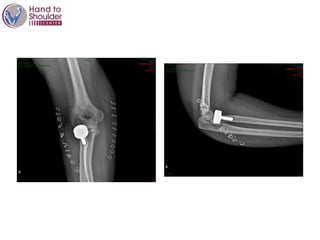

DAY 1

Stabilty

Result

@3 months

RESULTS 6 MONTHS